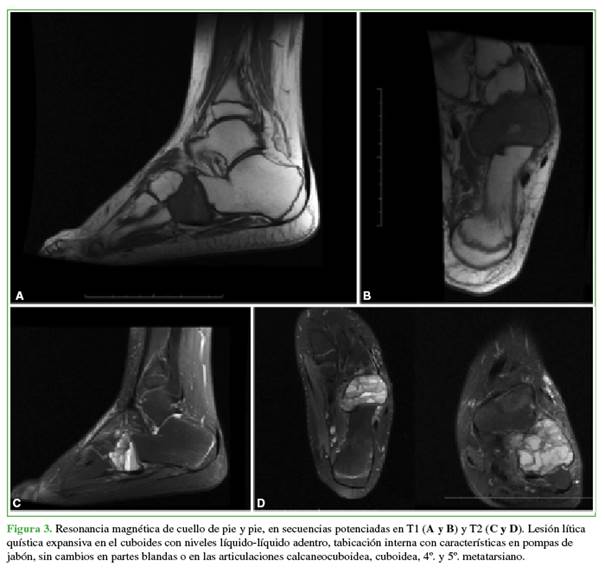

Ante una tumoración que impresionaba de estirpe ósea en un adolescente, se lo evalúo siguiendo el algoritmo clásico de nuestra institución: radiografías de la región afectada, análisis de sangre con relevo infeccioso y resonancia magnética (Figura 3).

La fase evolutiva del QOA se puede clasificar de acuerdo con los estadios de Enneking; en nuestro caso, correspondía a un estadio 2 (activo).